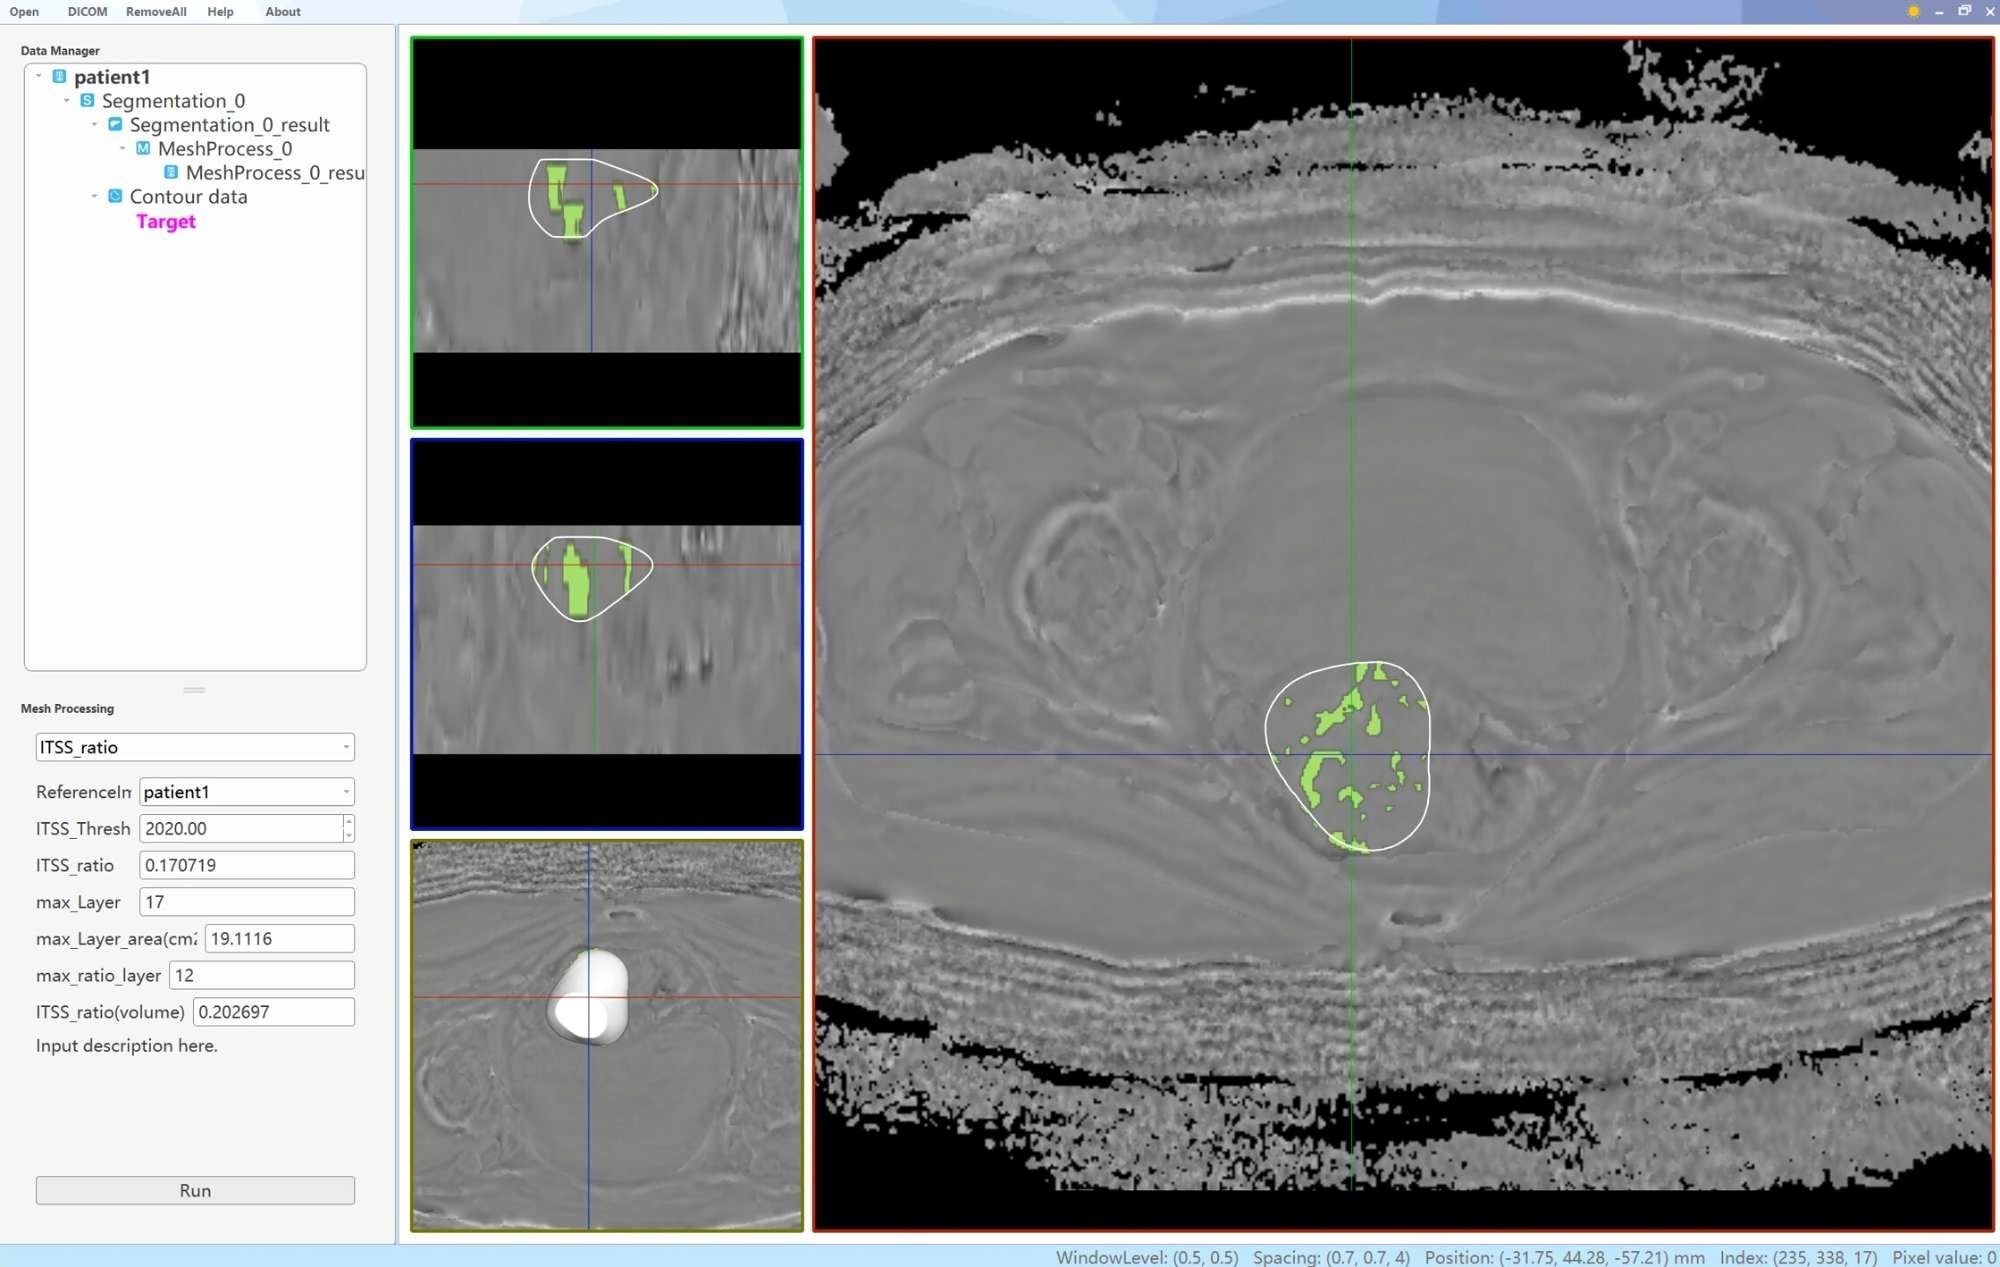

Two physicians, each with 6 and 11 years of experience in uterine MRI imaging diagnosis, utilized a double-blind method to identify tumor lesions. Referring to T2WI, DWI and apparent diffusion coefficient maps, the ROIs were delineated using an interactive semi-automatic method from the first to the last layer of the lesions on the phase maps. The edges of the lesions were defined based on DCE-MRI, with the ROIs outlined within 0.5 cm of the tumor edge to minimize volume effects. Therefore, lesions with a narrow range were excluded to ensure the accuracy of lesion delineation and the reliability of subsequent quantitative analysis. Upon completion of the delineations, three-dimensional volumes of interest were generated using the AS software. Subsequently, a plug-in within the AS software was utilized to determine the ITSS regions in the volumes of interest by establishing a threshold value of 2020. The ITSS ratios were then automatically calculated, including the ratio of the ITSS area in the maximum ITSS layer to the tumor area at that layer (intratumoral susceptibility signal sectional, ITSSs) and the ratio of tumor ITSS volume to the whole tumor volume (intratumoral susceptibility signal volume, ITSSv), as depicted in Figure 2.

Figure 2

Medical imaging software interface displaying three MRI slices of a brain with segmentation highlights in green. The slices are labeled and outlines are drawn on certain areas. Data parameters are visible on the left panel.

Figure 2. A schematic diagram of the AS software was utilized to calculate the tumor ITSS ratio. By employing the interpolation and labeling tools within the AS software, the ITSS ratio within the ROI was determined. The ITSS ratio is operationally defined as the ratio of pixels exhibiting low signal intensity within the ROI to the total number of pixels present within the ROI.